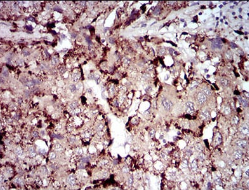

PLA2G12A Mouse Monoclonal antibody[3H291]

Secreted phospholipase A2 (sPLA2) enzymes liberate arachidonic acid from phospholipids for production of eicosanoids and exert a variety of physiologic and pathologic effects. Group XII sPLA2s, such as PLA2G12A, have relatively low specific activity and are structurally and functionally distinct from other sPLA2s

Immunogen:    Purified recombinant fragment of human PLA2G12A (AA: 21-189) expressed in E. Coli.

IHC    1/200 - 1/1000